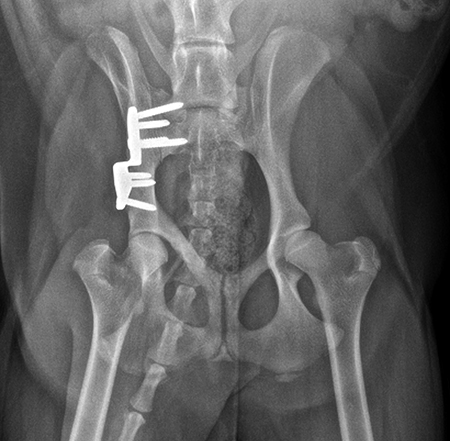

Angles of subluxation (10°) and reduction (30°) of the right hip were measured under anesthesia and the patient was placed in dorsal recumbency. A 7 mm portion of the right pubic body was excised. The patient was repositioned into lateral recumbency. A right ilial osteotomy was made immediately caudal to the sacrum. A 25° DPO/TPO plate was attached to the caudal ilial bone segment using locking 3.5 mm screws in the three stacked combi holes. The caudal acetabular segment was rotated laterally until the cranial aspect of the plate was in contact with the lateral aspect of the cranial ilial segment. The osteotomy site was compressed, and the plate was secured to the cranial ilial bone segment using a 3.5 mm cortical screw in the LCP combi hole in the cranial side of the plate. Three additional 3.5 mm locking screws were placed in the remaining stacked combi holes in the cranial segment of the plate.

Postoperative radiographs revealed reduction in subluxation with capture of the femoral head in the right coxofemoral joint (Fig 4). Palpation of the hip revealed good stability of the right hip. Activity was restricted to leash walk only for 6 weeks postoperatively. Radiographic examination 7 weeks following surgery revealed healing of the ilial osteotomy, stable implants, and excellent coxofemoral conformation and stability (Fig 5).